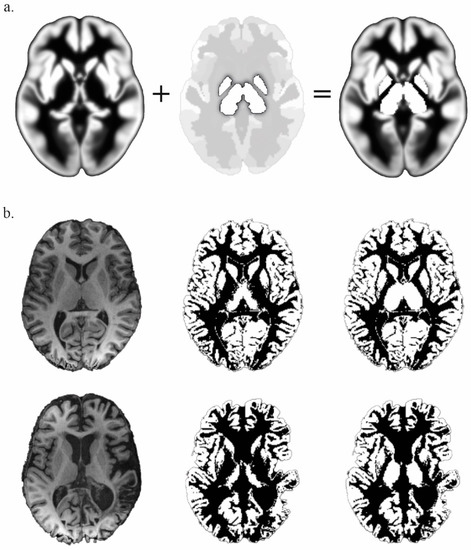

- Lorio, S.; Fresard, S.; Adaszewski, S.; Kherif, F.; Chowdhury, R.; Frackowiak, R.; Ashburner, J.; Helms, G.; Weiskopf, N.; Lutti, A.; et al. New tissue priors for improved automated classification of subcortical brain structures on MRI. NeuroImage 2016, 130, 157–166. [Google Scholar] [CrossRef]

- Whitfield-Gabrieli, S.; Nieto-Castanon, A. Conn: A functional connectivity toolbox for correlated and anticorrelated brain networks. Brain Connect. 2012, 2, 125–141. [Google Scholar] [CrossRef]